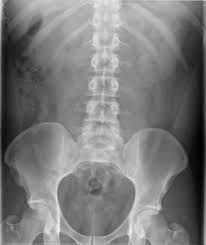

Kub radiography is a non invasive diagnostic tool that uses x ray imaging to view the kidneys ureters and bladder the organs in which it receives its name.

Kub kidney stones x ray. It can also be used to assess positioning of indwelling devices such as ureteral stent an indwelling tube placed in the ureter to treat obstruction. Meaning purpose procedure contrast cost. Kub study the kidney ureter and bladder kub study is a diagnostic x ray image that can detect the presence of kidney stones.

Ct scan kub means computed tomography of kidney ureters and bladder. It is a ct scan of kidneys bladder and ureters. Urolithiasis refers to the presence of calculi anywhere along the course of the urinary tracts for the purpose of the article the terms urolithiasis nephrolithiasis and renal kidney stones are used interchangeably although some authors have slightly varying definitions of each.

Definition a kidney ureter and bladder kub x ray study is an abdominal x ray. Find kidney stones stock images in hd and millions of other royalty free stock photos illustrations and vectors in the shutterstock collection. A kub x ray may be taken to evaluate the urinary tract before other diagnostic procedures are performed.

In addition you may have to get x ray of the abdomen called kub for kidney ureter and bladder and an ultrasound examination to see the location of the stone in the urinary tract. The other common study for kidney stones are plain x rays of the abdomen known as kub s which stands for kidney ureter bladder. A kidney ureter and bladder kub study is an x ray study that allows your doctor to assess the organs of your urinary and gastrointestinal systems.

The x ray beams are able to create a 2d image of organs inside. Ultrasound is a third option. Despite its name kub does not show the ureters and only sometimes shows the kidneys and bladder and even then with uncertainty.